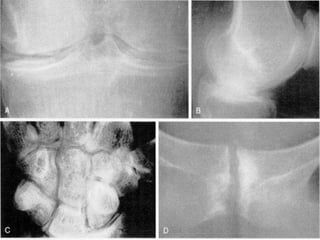

A , Acute pseudogout.  B , Pseudo-osteoarthritis.  C , Pseudo-rheumatoid arthritis with boutonniere deformity.  D , Pseudo-rheumatoid arthritis showing ulnar deviation, interosseous muscle atrophy, and metacarpophalangeal and wrist joint involvement. The patients in  A ,  C , and  D  are siblings.

Radiographic features knee menisci and articular cartilage triangular ligaments of the radiocarpal joint fibrocartilage of the symphysis pubis

A , Acutepseudogout. B , Pseudo-osteoarthritis. C , Pseudo-rheumatoid arthritis with boutonniere deformity. D , Pseudo-rheumatoid arthritis showing ulnar deviation, interosseous muscle atrophy, and metacarpophalangeal and wrist joint involvement. The patients in A , C , and D are siblings.

Radiographic features kneemenisci and articular cartilage triangular ligaments of the radiocarpal joint fibrocartilage of the symphysis pubis